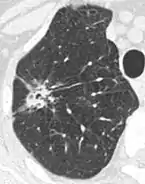

- Pleural retraction is far more common in cancers.[9] It is the pulling of visceral pleura towards the nodule.[9]

Nodule with pleural retraction.[9]

In this case, pleural retraction is seen as a triangular fat component.[9]